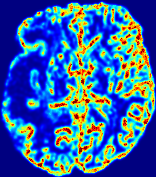

4.3.2 Diffusion Imaging via Advection-Diffusion

Slice #1Slice #2Slice #3Slice #4Slice #5Slice #6Dgtsuperscript𝐷gtD^{\text{gt}}Refer to captionRefer to captionRefer to captionRefer to captionRefer to captionRefer to captionDestsuperscript𝐷estD^{\text{est}}Refer to captionRefer to captionRefer to captionRefer to captionRefer to captionRefer to captionRefer to caption0.300.300.300.240.240.240.180.180.180.120.120.120.060.060.060.000.000.00(mm2/s)𝑚superscript𝑚2𝑠(mm^{2}/s)𝐕est𝟐subscriptnormsuperscript𝐕est2\|\bf{V}^{\text{est}}\|_{2}Refer to captionRefer to captionRefer to captionRefer to captionRefer to captionRefer to captionRefer to caption0.00300.00300.00300.00240.00240.00240.00180.00180.00180.00120.00120.00120.00060.00060.00060.00000.00000.0000(mm/s)𝑚𝑚𝑠(mm/s)

Figure 15: PIANO identifiability testing: diffusion imaging via advection-diffusion. Top row shows Dgtsuperscript𝐷gtD^{\text{gt}} used for simulating ground truth pure diffusion. Rows below show the estimated Destsuperscript𝐷estD^{\text{est}} and 𝐕est2subscriptnormsuperscript𝐕est2\|{\bf{V}}^{\text{est}}\|_{2} on corresponding slices. Note that the plotted value scale for 𝐕est2subscriptnormsuperscript𝐕est2\|{\bf{V}}^{\text{est}}\|_{2} is 0.01 of that for Dgtsuperscript𝐷gtD^{\text{gt}} and Destsuperscript𝐷estD^{\text{est}}.

Similarly, we test the behavior of PIANO when estimating both advection and diffusion from a pure diffusion-driven process. The goal is to determine if PIANO is able to recognize that there is only diffusion governing the given concentration time-series. We use the same ‘Diffusion Imaging’ data simulation of Sec. 4.2.1 as the concentration dataset, PIANO estimates both velocity 𝐕estsuperscript𝐕est{\bf{V}}^{\text{est}} and diffusivity Destsuperscript𝐷estD^{\text{est}}. Estimation results in Fig. 15 confirm PIANO’s identifiability again: the estimated 𝐕est2subscriptnormsuperscript𝐕est2\|{\bf{V}}^{\text{est}}\|_{2} is almost invisible compared to Destsuperscript𝐷estD^{\text{est}}, even plotted with a 1%percent11\% value range compared to that for Destsuperscript𝐷estD^{\text{est}}. On the other hand, Destsuperscript𝐷estD^{\text{est}} achieves comparable estimation performance as ‘Diffusion Imaging via Diffusion’ in which PIANO predicts Destsuperscript𝐷estD^{\text{est}} alone (shown in Fig. 13).